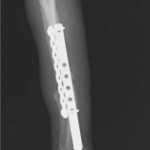

脛骨骨折 : 症例1 | 症例2 | 症例3 | 症例4 | 症例5

Advanced Locking plate system と Locking compression plate system

当院ではAdvanced Locking plate system(ALPS)と、Locking compression plate system(LCPS)という骨接合法で骨折症例の治療を行っています。

Locking Compression Plate

LCPは、スクリュー(ネジ)とプレート(金属の板)をロックする特殊な構造により骨折部位を固定する新しい世代のプレートシステムです。ひとつのホールでロッキングスクリューとスタンダードスクリューの使用を選択できるユニークな構造をしているため、骨折断端間の圧迫を目的とした従来型プレート固定法に加え、高い角度安定性を有するロッキングスクリューを用いた固定法の選択が可能です。従来のプレートシステムでは困難だった部分の骨折や癒合不全の症例に高い治療効果をもたらします。